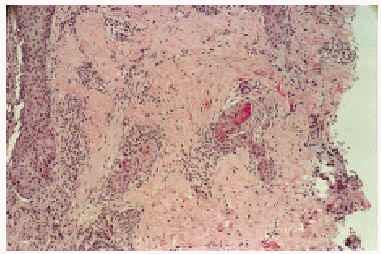

Cinco días después del final de la radioterapia la niña es hospitalizada por neutropenia febril con foco respiratorio, iniciándose tratamiento con cefepime y codeína. Al día siguiente se observó la aparición de unas placas eritematovioláceas, conformadas por micropápulas no foliculares, distribuidas en la región lumbar y en la zona del abdomen, con predilección por los bordes de la cicatriz de laparotomía (figs. 1 y 2). En el estudio histopatológico se evidenció una metaplasia escamosa madura de las porciones rectas de los conductos de las glándulas ecrinas sin afectación de los ovillos (fig. 3). Se observaban asimismo frecuentes células necróticas, queratinización de las luces y aislados queratogranulomas que entraban en contacto con la luz glandular (figs. 4 y 5). El diagnóstico histológico fue de siringometaplasia escamosa ecrina. La enferma continuó tratamiento quimioterápico, a pesar de lo cual las lesiones evolucionaron espontáneamente hacia la curación en un período aproximado de 1 mes, quedando una hiperpigmentación residual que se fue borrando paulatinamente.

Fig. 3.--Panorámica. Porción recta de conductos de glándulas ecrinas con metaplasia escamosa.